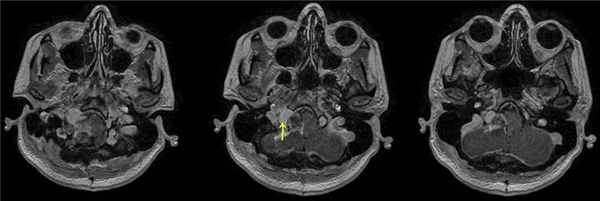

При проведении диффузионно-тензорной трактографии реконструированы каудальная группа нервов и кортикоспинальный тракт. Последний компримирован опухолью и оттеснен влево. На нижнем полюсе располагались корешки верхних шейных сегментов спинного мозга и подъязычного нерва. Языкоглоточный и блуждающий нерв располагались на верхнем полюсе опухоли и были деформированы (рис. 3). Рис. 3. Диффузионно-тензорная трактография головного мозга пациентки В. до операции. Определен кортикоспинальный тракт в стволе головного мозга, на верхнем полюсе опухоли располагаются языкоглоточный и блуждающий нервы, по переднему полюсу проходят добавочный нерв и корешок СI. а — кортикоспинальный тракт, б — корешки IX, X, XI черепно-мозговых нервов, в — акустико-фациальная группа нервов, г — опухоль.